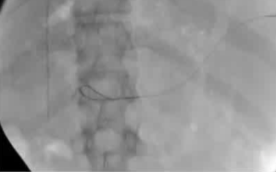

该程序包含以下步骤: 经脾脏入路:在超声引导下,刺穿脾静脉内的一个实质内分支。 在通过脾静脉造影确认了静脉通路后,导管和导丝被推进,以穿过脾静脉并抵达血栓化的门静脉。在门静脉/右门静脉分支处放置圈套器,为TIPS穿刺精准定位。TIPS穿刺圈套器,并穿过圈套器完成TIPS

步骤: 鉴于慢性血栓形成的复杂性: 一种经脾脏途径的门静脉再通术(PVR)。 随后是经颈静脉肝内门体分流术 。

通过经颈静脉肝内门体分流术(TIPS)治疗慢性门静脉血栓时所涉及的技术复杂性和决策难题,尤其是在标准方法因血栓程度过重而无法实施的情况下更是如此。 采用脾经脏穿刺术治疗门静脉高压症的方法证明能够有效克服这些难题,从而成功实施了经颈静脉肝内门体分流术(TIPS)。 PVR-TIPS 作为一线治疗方案:PVR-TIPS 为慢性门静脉血栓的治疗提供了一种技术上可行的解决方案,克服了标准 TIPS 安装所面临的难题。 持久效果:该干预措施不仅恢复了门静脉的血流,而且在后续随访中还显示出持续的通畅性以及血栓的完全消散。